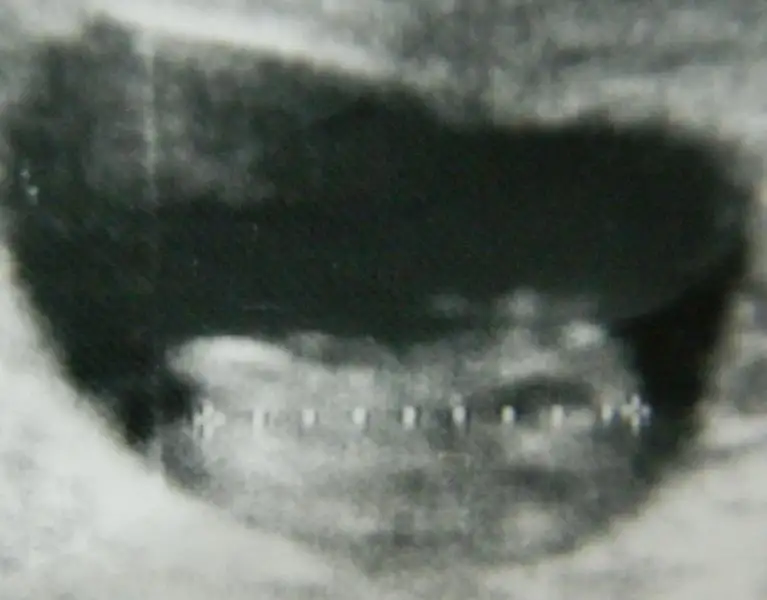

o beyazlık bacak kemiği mi nub mu sizce.haftaya belli olacak cinsiyeti .belli olunca geri dönerim.lütfen yorum yapın teyzeleri

yorum için teşekkürler zeynepzzz.eşim de o kadar dik nub olmaz kemik o demişti.bakalım haftaya öğreniriz inşallah cinsiyetini kız veya erkek sağlıklı olsun da .rabbim herkese nasip eder inşalllah bi evlat

Amin canim saglikla kucaginada al insallah annesine de el sallamis ogrenince haber ver icimden kiz gecti benim